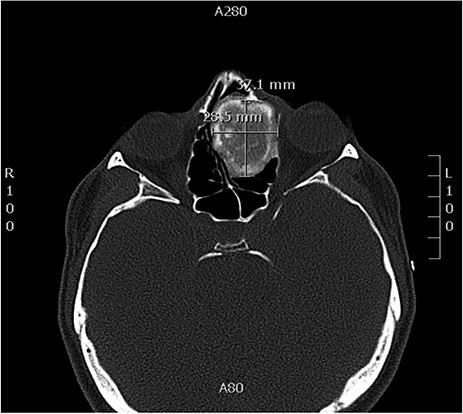

A 34-years-old man presented with left-sided facial pain, headache and nasal obstruction for a long duration, with no history of bleeding per nose, nor blurring of vision. Upon examination, there was a large left nasal cavity bony outgrowth pushing the middle turbinate and pushing the nasal septum to the right side (Fig. 1). CT scan of the paranasal sinuses showed a large mass centered in the left anterior ethmoid sinus, the mass measures 3.7 × 2.9 cm (trans-axial) (Fig. 2) and 3.7 × 5.2 cm (coronal) (Fig. 3), it has a heterogeneous density with calcified and soft-tissue component. The calcified component is in the periphery with central soft tissue density. The mass resulted in remodeling of adjacent bones with nasal septal deviation to the right, it extended superiorly to involve the frontal sinuses as well as invading the left cribriform plate and intracranial extension (Fig. 4), it extended inferiorly displacing the medial wall of the left maxillary antrum. The medial aspect of the mass caused remodeling of the medial wall of the left orbital cavity with bulging and displacement of the medial rectus muscle. The mass resulted in obstruction of the left frontal sinus.

Axial CT image of the sinuses showing a mass filling the left ethmoidal sinus.